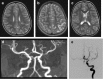

Stroke is as common as brain tumor in children. The etiology of childhood arterial ischemic stroke (AIS) appears to be multifactorial, resulting from the interaction between genetic predisposition and environmental triggers. The risk factors for AIS in children are markedly different from the atherosclerotic risk factors in adults. Trauma and infections have been identified as associations in previous studies and are exposures of particular interest because of their increased prevalence in the children. The aim of this review article is to provide an overview of the research studies that have addressed the role of infections and trauma in pediatric AIS.